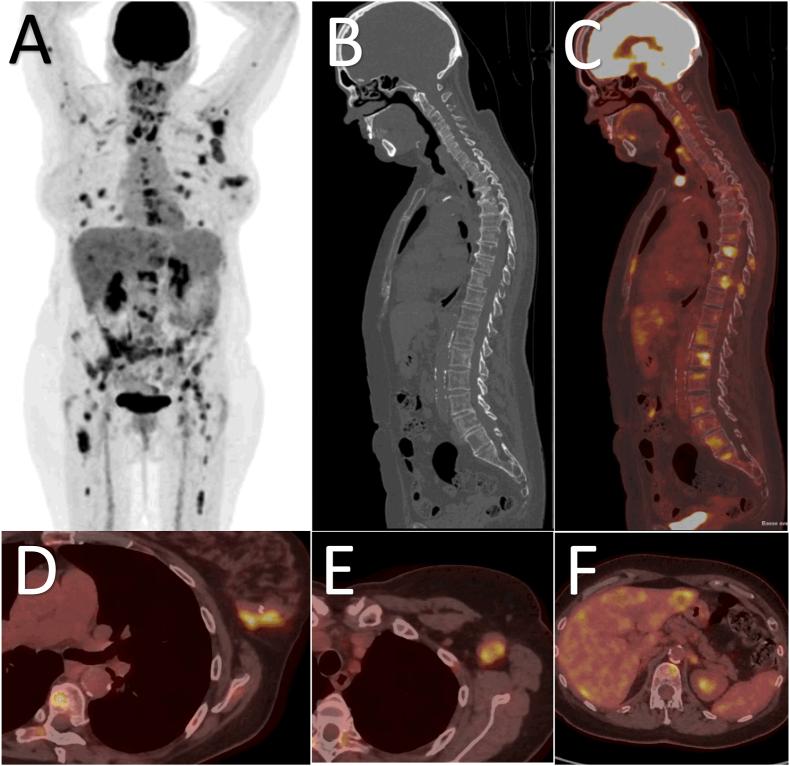

Regarding initial staging of patients with NST BC, [F]FDG PET/CT is the preferred modality in the EANM-SNMMI guideline, showing superiority as a single modality to a combination of contrast-enhanced CT of thorax-abdomen-pelvis plus bone scan in head-to-head comparisons and a randomized study. Its use is recommended in patients with clinical stage IIB or higher and may be useful in certain stage IIA cases of NST BC. In NCCN, ESMO, and ABC guidelines, [F]FDG PET/CT is instead recommended as complementary to conventional imaging to solve inconclusive findings, although ESMO and ABC also suggest [F]FDG PET/CT can replace conventional imaging for staging patients with high-risk and metastatic NST BC. During follow up, NCCN and ESMO only recommend diagnostic imaging if there is suspicion of recurrence. Similarly, EANM-SNMMI states that [F]FDG PET/CT is useful to detect the site and extent of recurrence only when there is clinical or laboratory suspicion of recurrence, or when conventional imaging methods are equivocal. The EANM-SNMMI guideline is the first to emphasize a role of [F]FDG PET/CT for assessing early metabolic response to primary systemic therapy, particularly for HER2+ BC and TNBC. In the metastatic setting, EANM-SNMMI state that [F]FDG PET/CT may help evaluate bone metastases and determine early response to treatment, in agreement with guidelines from ESMO.

对于 NST BC 患者的初始分期,[F]FDG PET/CT 是 EANM-SNMMI 指南中的首选方法,在头对头比较和随机研究中,作为单一方法,其显示出优于对比增强 CT 联合胸部-腹部-骨盆加骨扫描的优越性。建议在临床分期 IIB 或更高的患者中使用,并且在某些 NST BC 的 IIA 病例中可能有用。在 NCCN、ESMO 和 ABC 指南中,[F]FDG PET/CT 被建议作为常规成像的补充,以解决不确定的发现,尽管 ESMO 和 ABC 也建议[F]FDG PET/CT 可用于分期高危和转移性 NST BC 患者。在随访期间,NCCN 和 ESMO 仅建议在怀疑复发时进行诊断性影像学检查。同样,EANM-SNMMI 指出,只有在临床或实验室怀疑复发时,或当常规影像学方法不确定时,[F]FDG PET/CT 才有助于检测复发的部位和范围。EANM-SNMMI 指南是第一个强调[F]FDG PET/CT 在评估原发性全身治疗早期代谢反应中的作用的指南,特别是对于 HER2+BC 和三阴性 BC。在转移性环境中,EANM-SNMMI 指出,[F]FDG PET/CT 可帮助评估骨转移并确定对治疗的早期反应,与 ESMO 的指南一致。